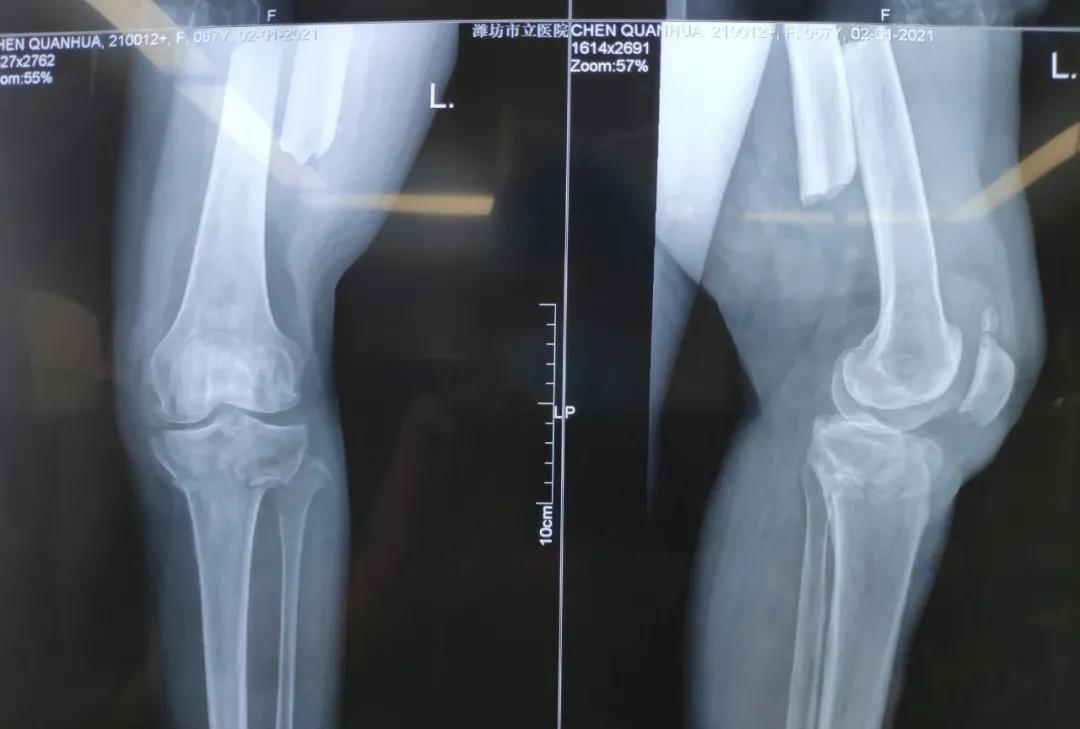

2021年1月2日下午,濰坊市市立醫(yī)院急診科接收了一位67歲的阿姨,阿姨是一位環(huán)衛(wèi)工人,在路邊清掃積雪時不慎被一輛汽車撞傷,致使其左脛骨平臺骨折、左股骨干骨折、左橈骨骨折,急需手術(shù)治療。

在快速做好精密的術(shù)前準(zhǔn)備后,2021年1月2日晚,創(chuàng)傷外科孫守全主任團(tuán)隊(duì)為阿姨行左脛骨平臺骨折、左股骨干骨折、左橈骨骨折切開復(fù)位內(nèi)固定術(shù)手術(shù),手術(shù)順利。術(shù)后阿姨的病情得到穩(wěn)定,在醫(yī)務(wù)人員的貼心服務(wù)和細(xì)心照料下,身體恢復(fù)狀態(tài)良好。